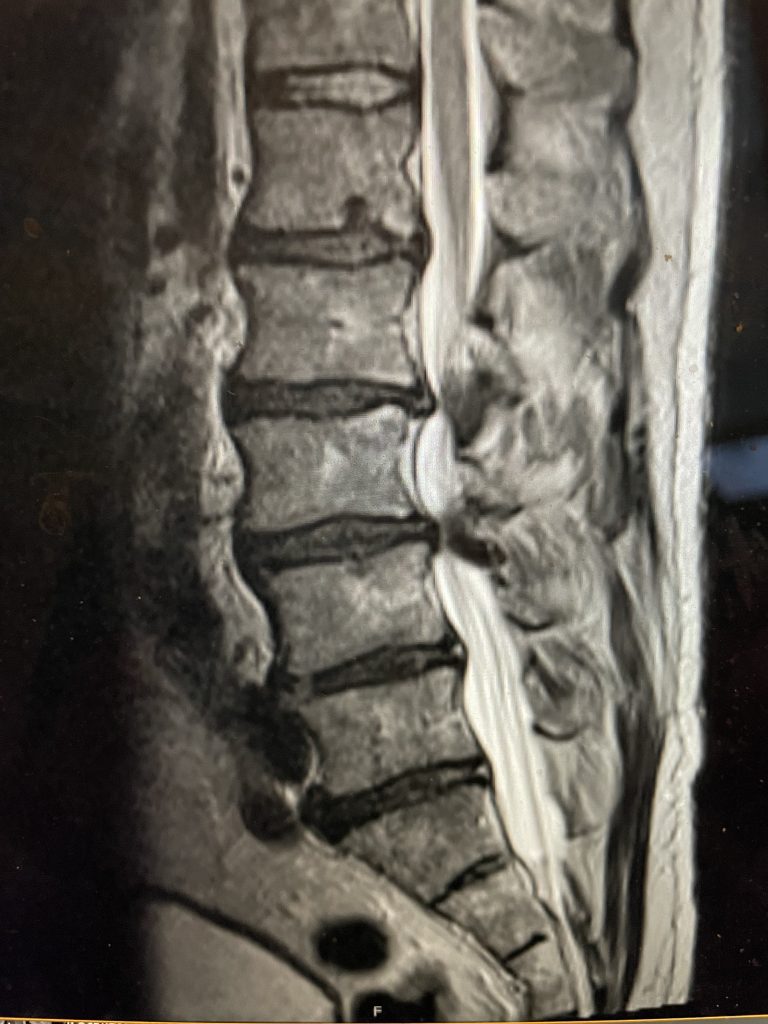

Figure 1. Sagittal T2-weighted MRI demonstrating severe L2-4 stenosis and slight grade 1 spondylolisthesis L3-4.

MRI demonstrated severe L3-4 stenosis with a grade 1 spondylolisthesis. He also had L2-3 stenosis. (Fig 1). On axial MRI (Fig 2) he had severe concentric stenosis at L3-4, but on careful examination it appeared that the right side had particular distortion of the anterior aspect of the thecal sac, perhaps secondary to a facet cyst. It seemed more likely coming off the facet joint and not a disc herniation. Although the right side was worse, most of his symptoms were on the left. Why does that happen? I don’t have a great explanation. Clearly the left side is also compressed but sometimes the body just chooses the side to be affected symptomatically when both sides are involved. This is true for compression of the spinal cord for instance in the cervical spine. What is not right, however, is that if a patient has a lateralized disc herniation and the opposite side is symptomatic and without compression, then one should not offer surgical treatment unless that disc is causing severe compression on one side with just less compression on the ipsilateral symptomatic side. Then one can argue that the pathology is having an effect on the opposite side if there is some degree of bilateral compression even if the ipsilateral symptomatic side is less compressed.